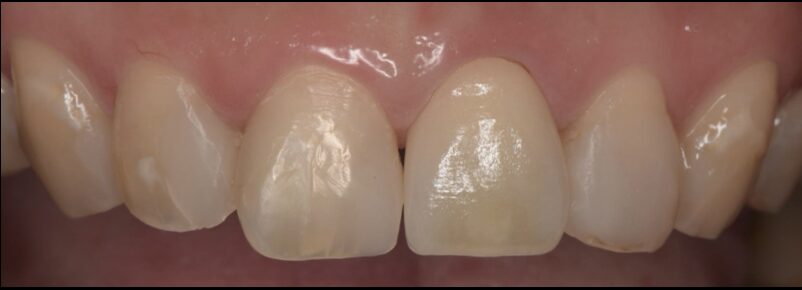

After

セラミックSET後